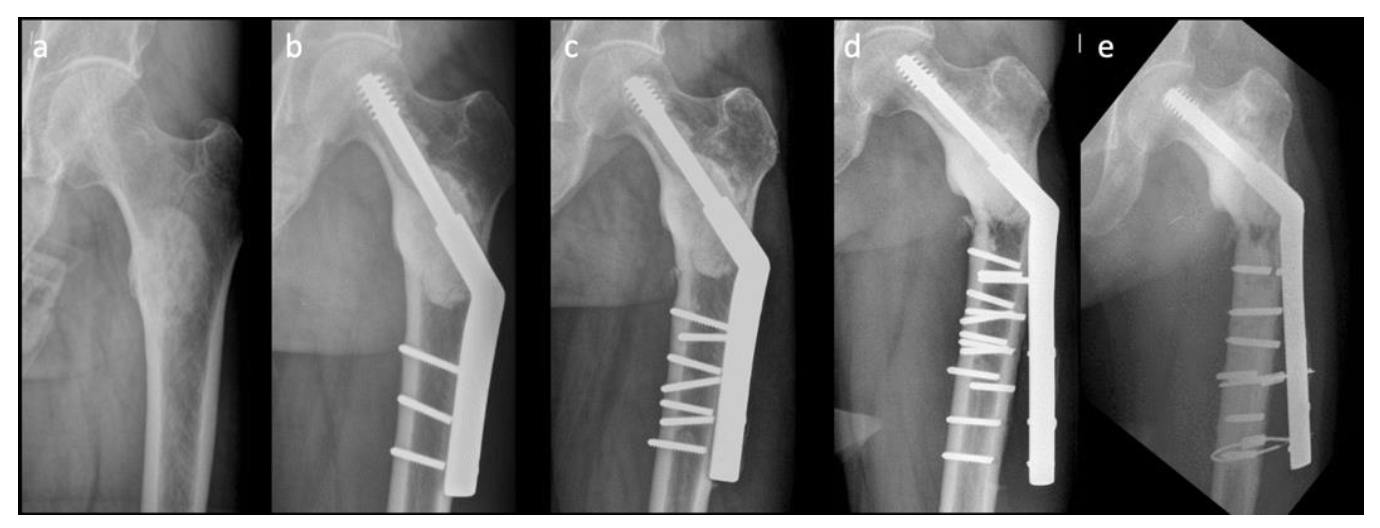

Nonetheless, there are drawbacks in using conventional SHS in the treatment of pathologically impending or actual peritrochanteric fractures. The complication rate with the SHS construct is reportedly as high as 42%, compared with that of EPR (3.1%) and IMN (6.1%); however, SHS remains the necessary choice for surgical treatment of pathologic peritrochanteric fractures [8]. Figure 1 shows a difficult case with multiple implant failures treated using conventional SHS technique complicated with cement augmentation loosening, non-union and broken screws, and all these increased difficulty in revision surgery. Longer SHS side plates are needed to provide better strength against the shearing force in each revision surgery. Therefore, in this retrospective comparative study, we compared two methods: a modified SHS technique augmented using cerclage reconstruction plates to reduce implant failure rate and to provide an alternative when performing revision ORIFs to treat patients with pathologically impending or actual peritrochanteric fractures caused by bone metastases, and conventional SHS. We also aimed to identify the factors that are associated with revision surgery.

Figure 1.

A difficult case with multiple implant failures: (a) preoperative X-ray image, (b) first-time implant failure, (c) second-time implant failure, (d) third-time implant failure, and (e) fourth-time implant failure.